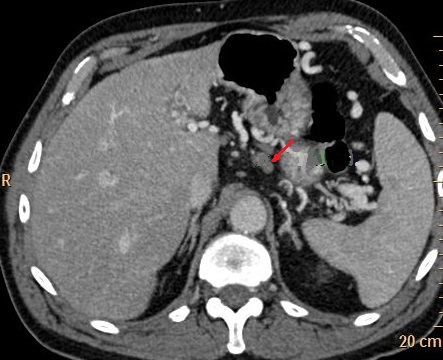

Image d'une pancreatite aigue

avec des foyers de absence de rehaussement a

hypodense apres de injection contrast intraveineuse

( fleche rouge ) . Image radiologique TDM phase

arteriel |

|

Aspect de reactionnel des

ganglions peri- pancreatique ( fleche rouge ) |